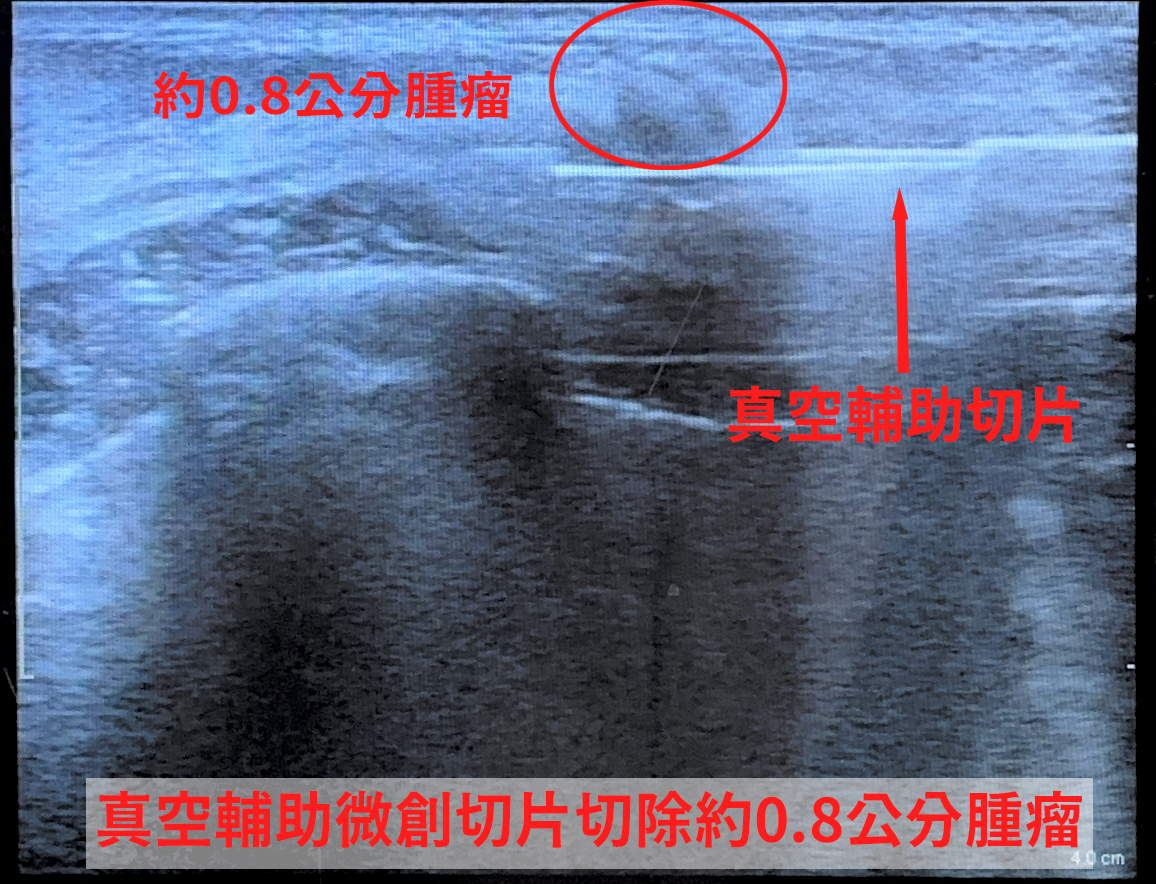

一名年僅24歲的年輕女性,近日因乳房疼痛就醫,求診中國醫藥大學新竹附設醫院乳房外科主任古君平,透過超音波檢查發現約0.8公分不規則邊緣腫瘤,且伴隨微鈣化。雖然初次以傳統粗針切片檢查結果為良性,但影像仍顯示有異常,醫師認為癌症的風險大概10%甚至50%,醫病溝通後,進一步以「真空輔助微創切片」取得更多組織,提升診斷準確度,也可同步完整移除腫瘤。

而以真空輔助微創手術,切開的傷口藏在乳房側面,或是在乳暈的邊緣,傷口大概0.3到0.5公分,比傳統的傷口小非常多,而且透過微創的切割,可以精準在超音波下判斷腫瘤位置,保留周邊乳腺組織,乳房外觀幾乎不受影響,乳房乳腺乳暈的破壞也比較少一點。手術時間約半小時即可完成,相比傳統2至3公分切口的手術,傷口更小、破壞更少,術後恢復快。